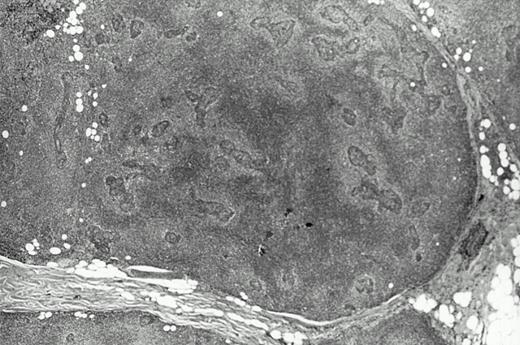

Two contralateral biopsy specimens of MESA-associated lesions from eight different patients were analyzed by a standard PCR technique for detecting clonal B cells. In seven of the eight cases, both of the contralateral biopsies, which are further described in Table 2, contained clones. The biopsies from one case showed only polyclonal B cells and were not further studied. With the exception of entries for patient HA, most of the other information in Table 2 can be found in our earlier study (see Table 7 in Quintana et al13) along with other clinical data for these patients. Biopsies with material available for analysis in this study were largely from parotid glands and the time intervals between the first and second biopsies ranged from several months to more than 10 years. Histologically, most of the biopsies met criteria considered to be diagnostic of low-grade MALT lymphoma by showing confluent areas of pale monocytoid cells (Fig 1). However, several of the biopsies showed only MESA with small nonconfluent halos of monocytoid cells around the lymphoepithelial lesions, which has been proposed to represent a precursor lesion or the earliest histologic sign of lymphoma. In one case (MA), both of the biopsies that were analyzed histologically showed only reactive MESA.

Histologic features of the low grade salivary gland MALT lymphoma from patient JA. Note the halos of pale monocytoid cells around lymphoepithelial lesions on the right that become more confluent particularly on the left.